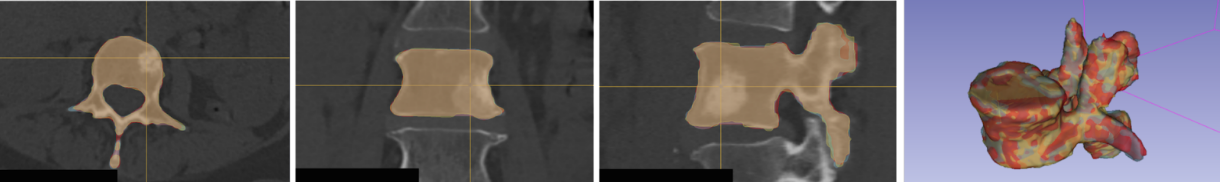

Accurate and reliable registration of longitudinal spine images is essential for assessment of disease progression and surgical outcome. Implementing a fully automatic and robust registration is crucial for clinical use, however, it is challenging due to substantial change in shape and appearance due to lesions. In this paper we present a novel method to automatically align longitudinal spine CTs and accurately assess lesion progression. Our method follows a two-step pipeline where vertebrae are first automatically localized, labeled and 3D surfaces are generated using a deep learning model, then longitudinally aligned using a Gaussian mixture model surface registration. We tested our approach on 37 vertebrae, from 5 patients, with baseline CTs and 3, 6, and 12 months follow-ups leading to 111 registrations. Our experiment showed accurate registration with an average Hausdorff distance of 0.65 mm and average Dice score of 0.92.